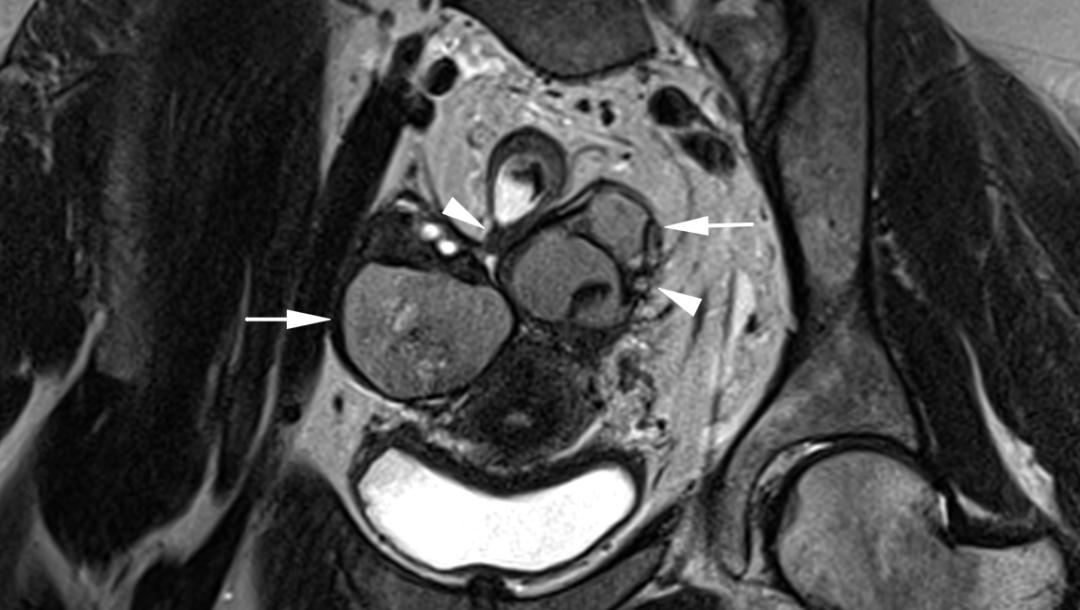

子宫内膜异位至双侧卵巢,T2WI 斜冠位和轴位双侧卵巢类圆形高低混杂信号结节,注意左侧卵巢子宫内膜异位症与乙状结肠之间线性低信号影,提示这些结构之间的粘连。